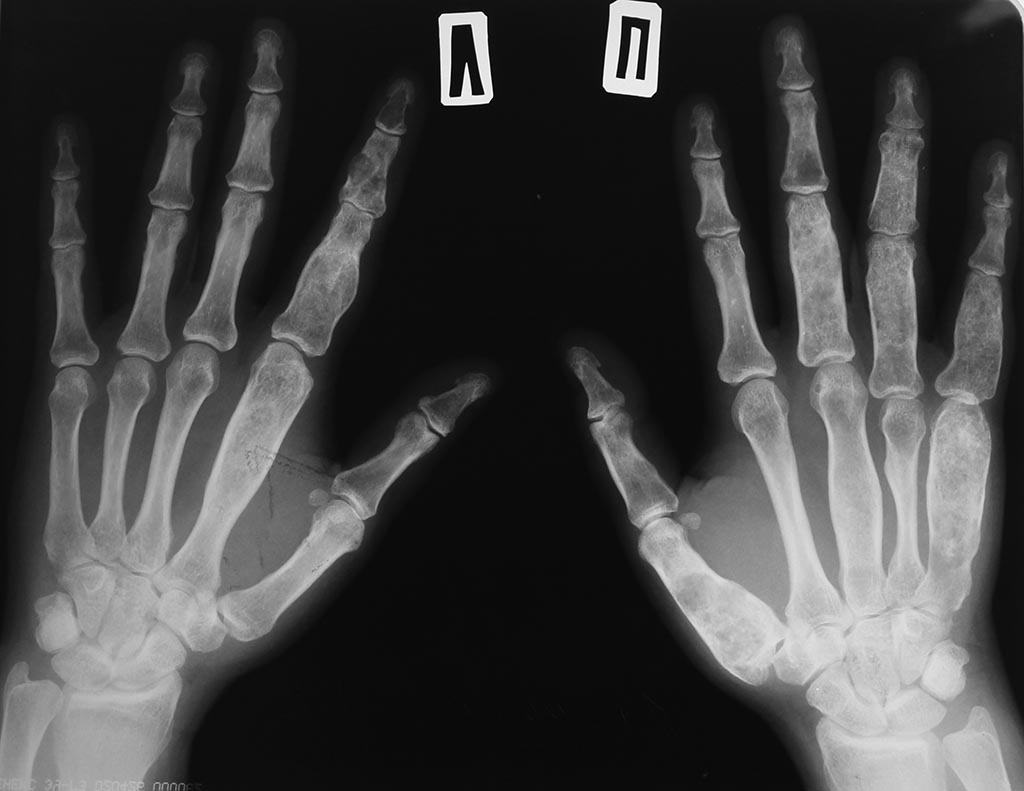

Обратилась пациента 44 годаОстеодисплазия - что это?

Болеет с 4 летнего возраста, множественные переломы пальцев кисти от

незначительных травм.

В детстве лечилась в Шумской больнице. После лечилась в ЦИТО у Зацепина

остановился процесс после позднего полового созревания и рождения

ребенка А пол года назад возобновился процесс. Был очередной перелом,

беспокоят боли. Карту с всеми заключниями ее потеряли в

поликлинике. Диагноз точно не знает. Остеодисплазия! Вопрос: что это?